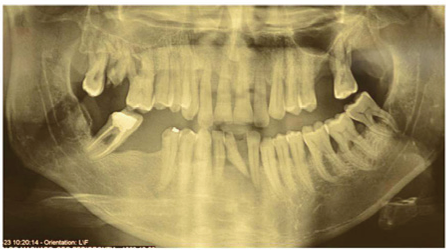

During the anamnesis, the patient did not report being a carrier of systemic diseases; declared him non-smoker. He reported regular tooth brushing three times a day with regular flossing and mouth washing. Asked about similar periodontal diseases in the family, he said he did not know. Radiographic examination revealed generalized vertical bone loss, being more localized in the molar and incisor regions. The diagnosis was aggressive periodontitis (Figure 3).

Figure 3 Radiography.

Extraoral examination was normal. During the intrabuccal examination, presence of several gingival recessions, periodontal clinical parameters were used: visible plaque index [VIP], gingival bleeding index [GBI], probing depth [PD] and clinical insertion oss [CAL]. Gingivitis induced by bacterial plaque and severe AgP was diagnosed. The presence of plaque visible in 41% of the faces and 35% of marginal bleeding justifies the diagnosis of gingivitis, the loss of insertion in all teeth, justifies the diagnosis of periodontitis. The presence of insertion loss between 1 and +10 mm in several teeth with a mean insertion loss of 6.61mm occurring in a period of maximum 20 years and degrees III furcation lesions in all molars in an adult indicates an important pattern of periodontal destruction, not compatible with slow and continuous progression of chronic periodontitis. Another factor that supports the diagnosis of aggressive periodontitis is the rapid progression of insertion loss, due to the presence of vertical bone loss identified in the radiographic examination [for example, teeth 12,11,24,47,42,31,36 and 37] (Figure 4 ).